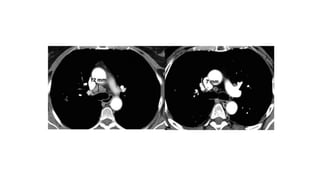

Chest x ray

• Measurable if lesion borders are clearly defined and

surrounded by aerated lung.

• Lesions bordering the thoracic wall are not suitable for

CT SCAN

• Preferred imaging modality

• CT scans of the thorax, abdomen, and pelvis should be contiguous

throughout the anatomic region of interest.

• The longest diameter of each target lesion should be selected in the

axial plane only.